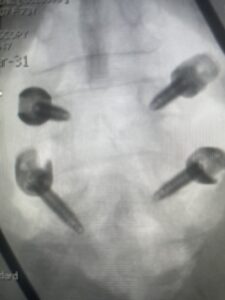

Fig 6: AP and lateral fluoroscopic images demonstrating pedicle screw placement in L3-4 fusion for spondylolisthesis.